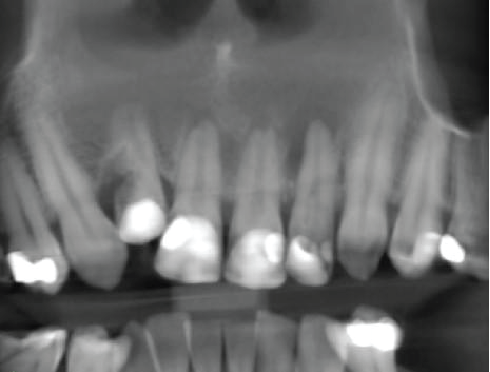

Panoramic reconstruction

Region scanned:

UR4 to UL6